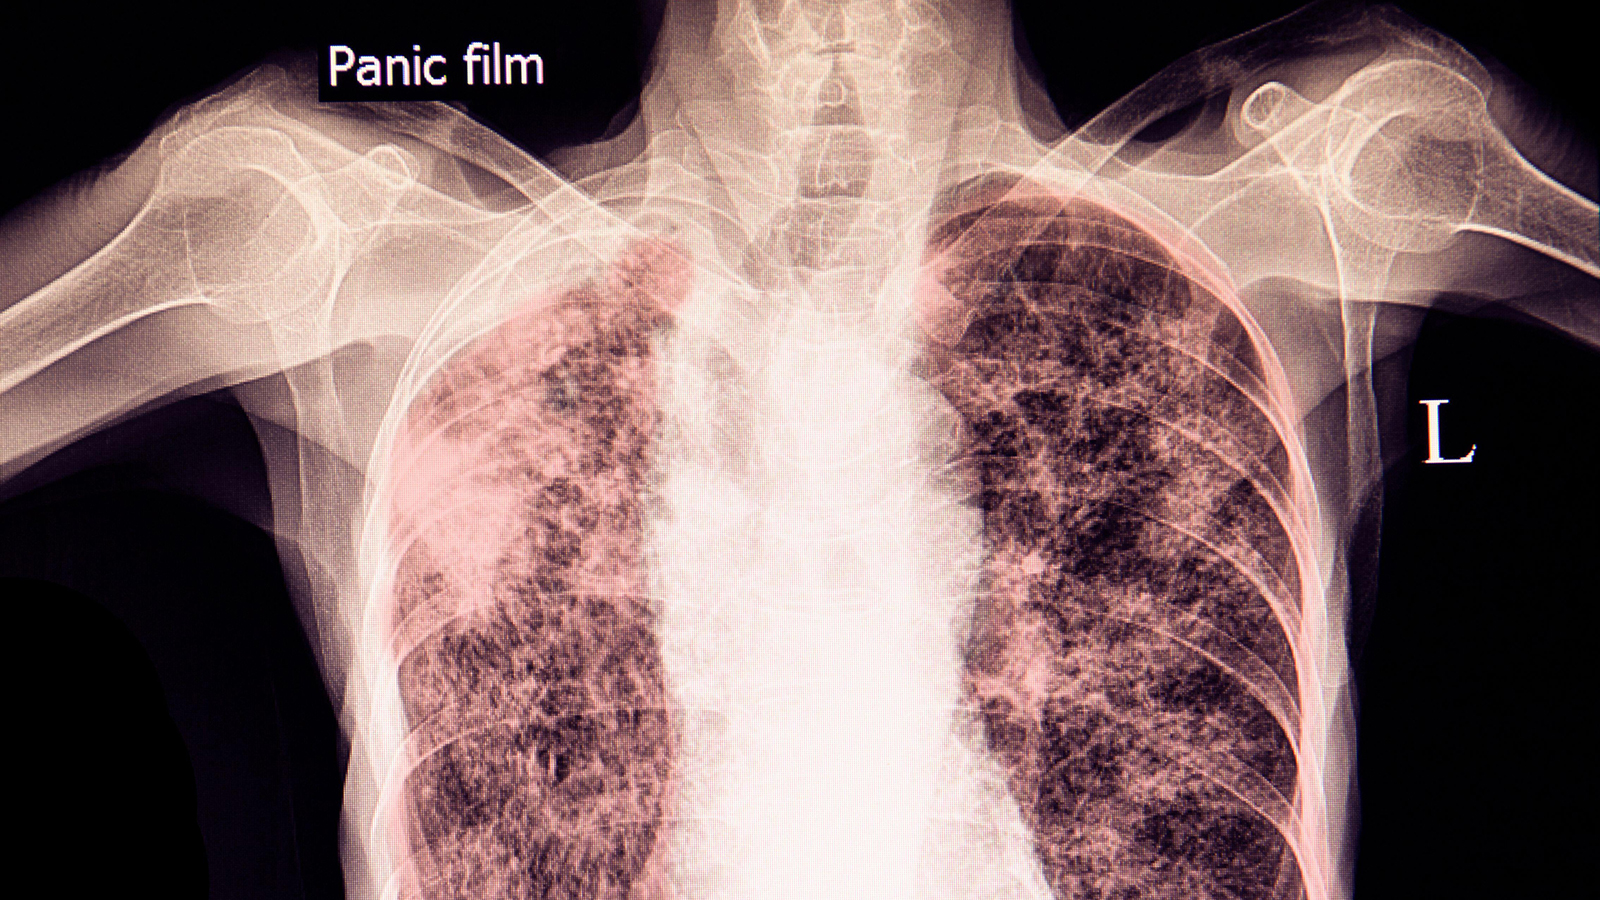

(MedPage Today) — Over the last few months, a woman from Tacoma, Washington has been widely featured in local and national media, including the New York Times, for refusing to take medication for active tuberculosis (TB).